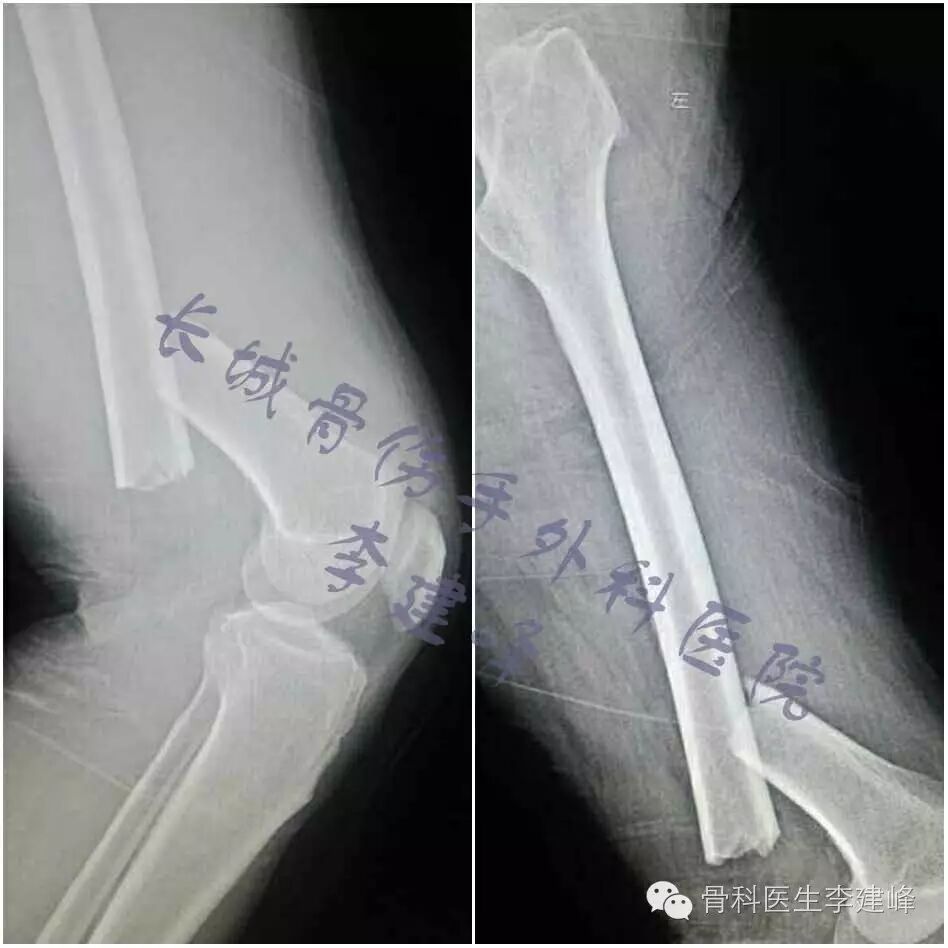

Five case :

术前

术后